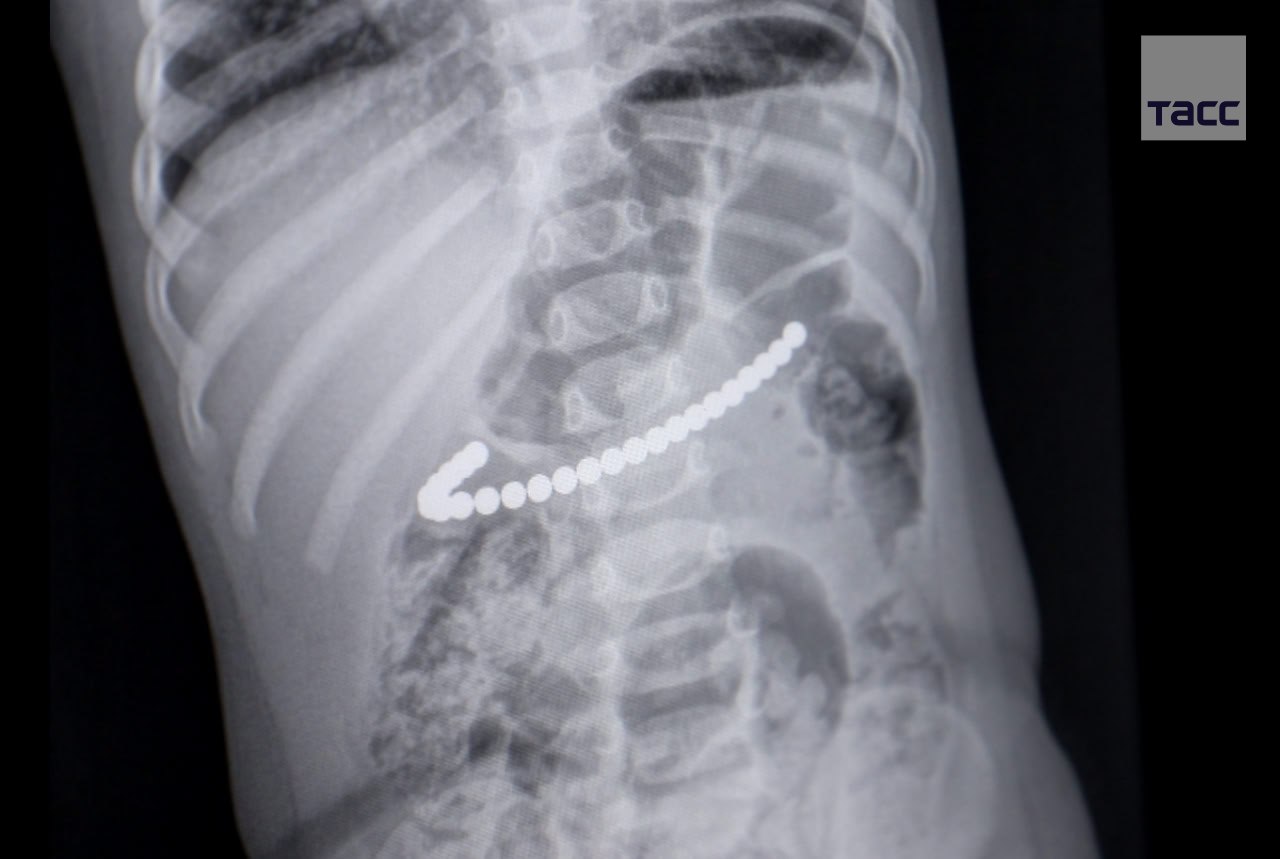

Врачи в Кемерове спасли годовалую девочку, которая проглотила 24 магнитных шарика, сообщает министр здравоохранения региона Андрей Тарасов.

Шарики были крепко соединены друг с другом в желудке ребенка в единую цепочку, которая одним концом уходила в область 12-перстной кишки. Медики извлекли их эндоскопическим путем.

Фото: Минздрав Кузбасса